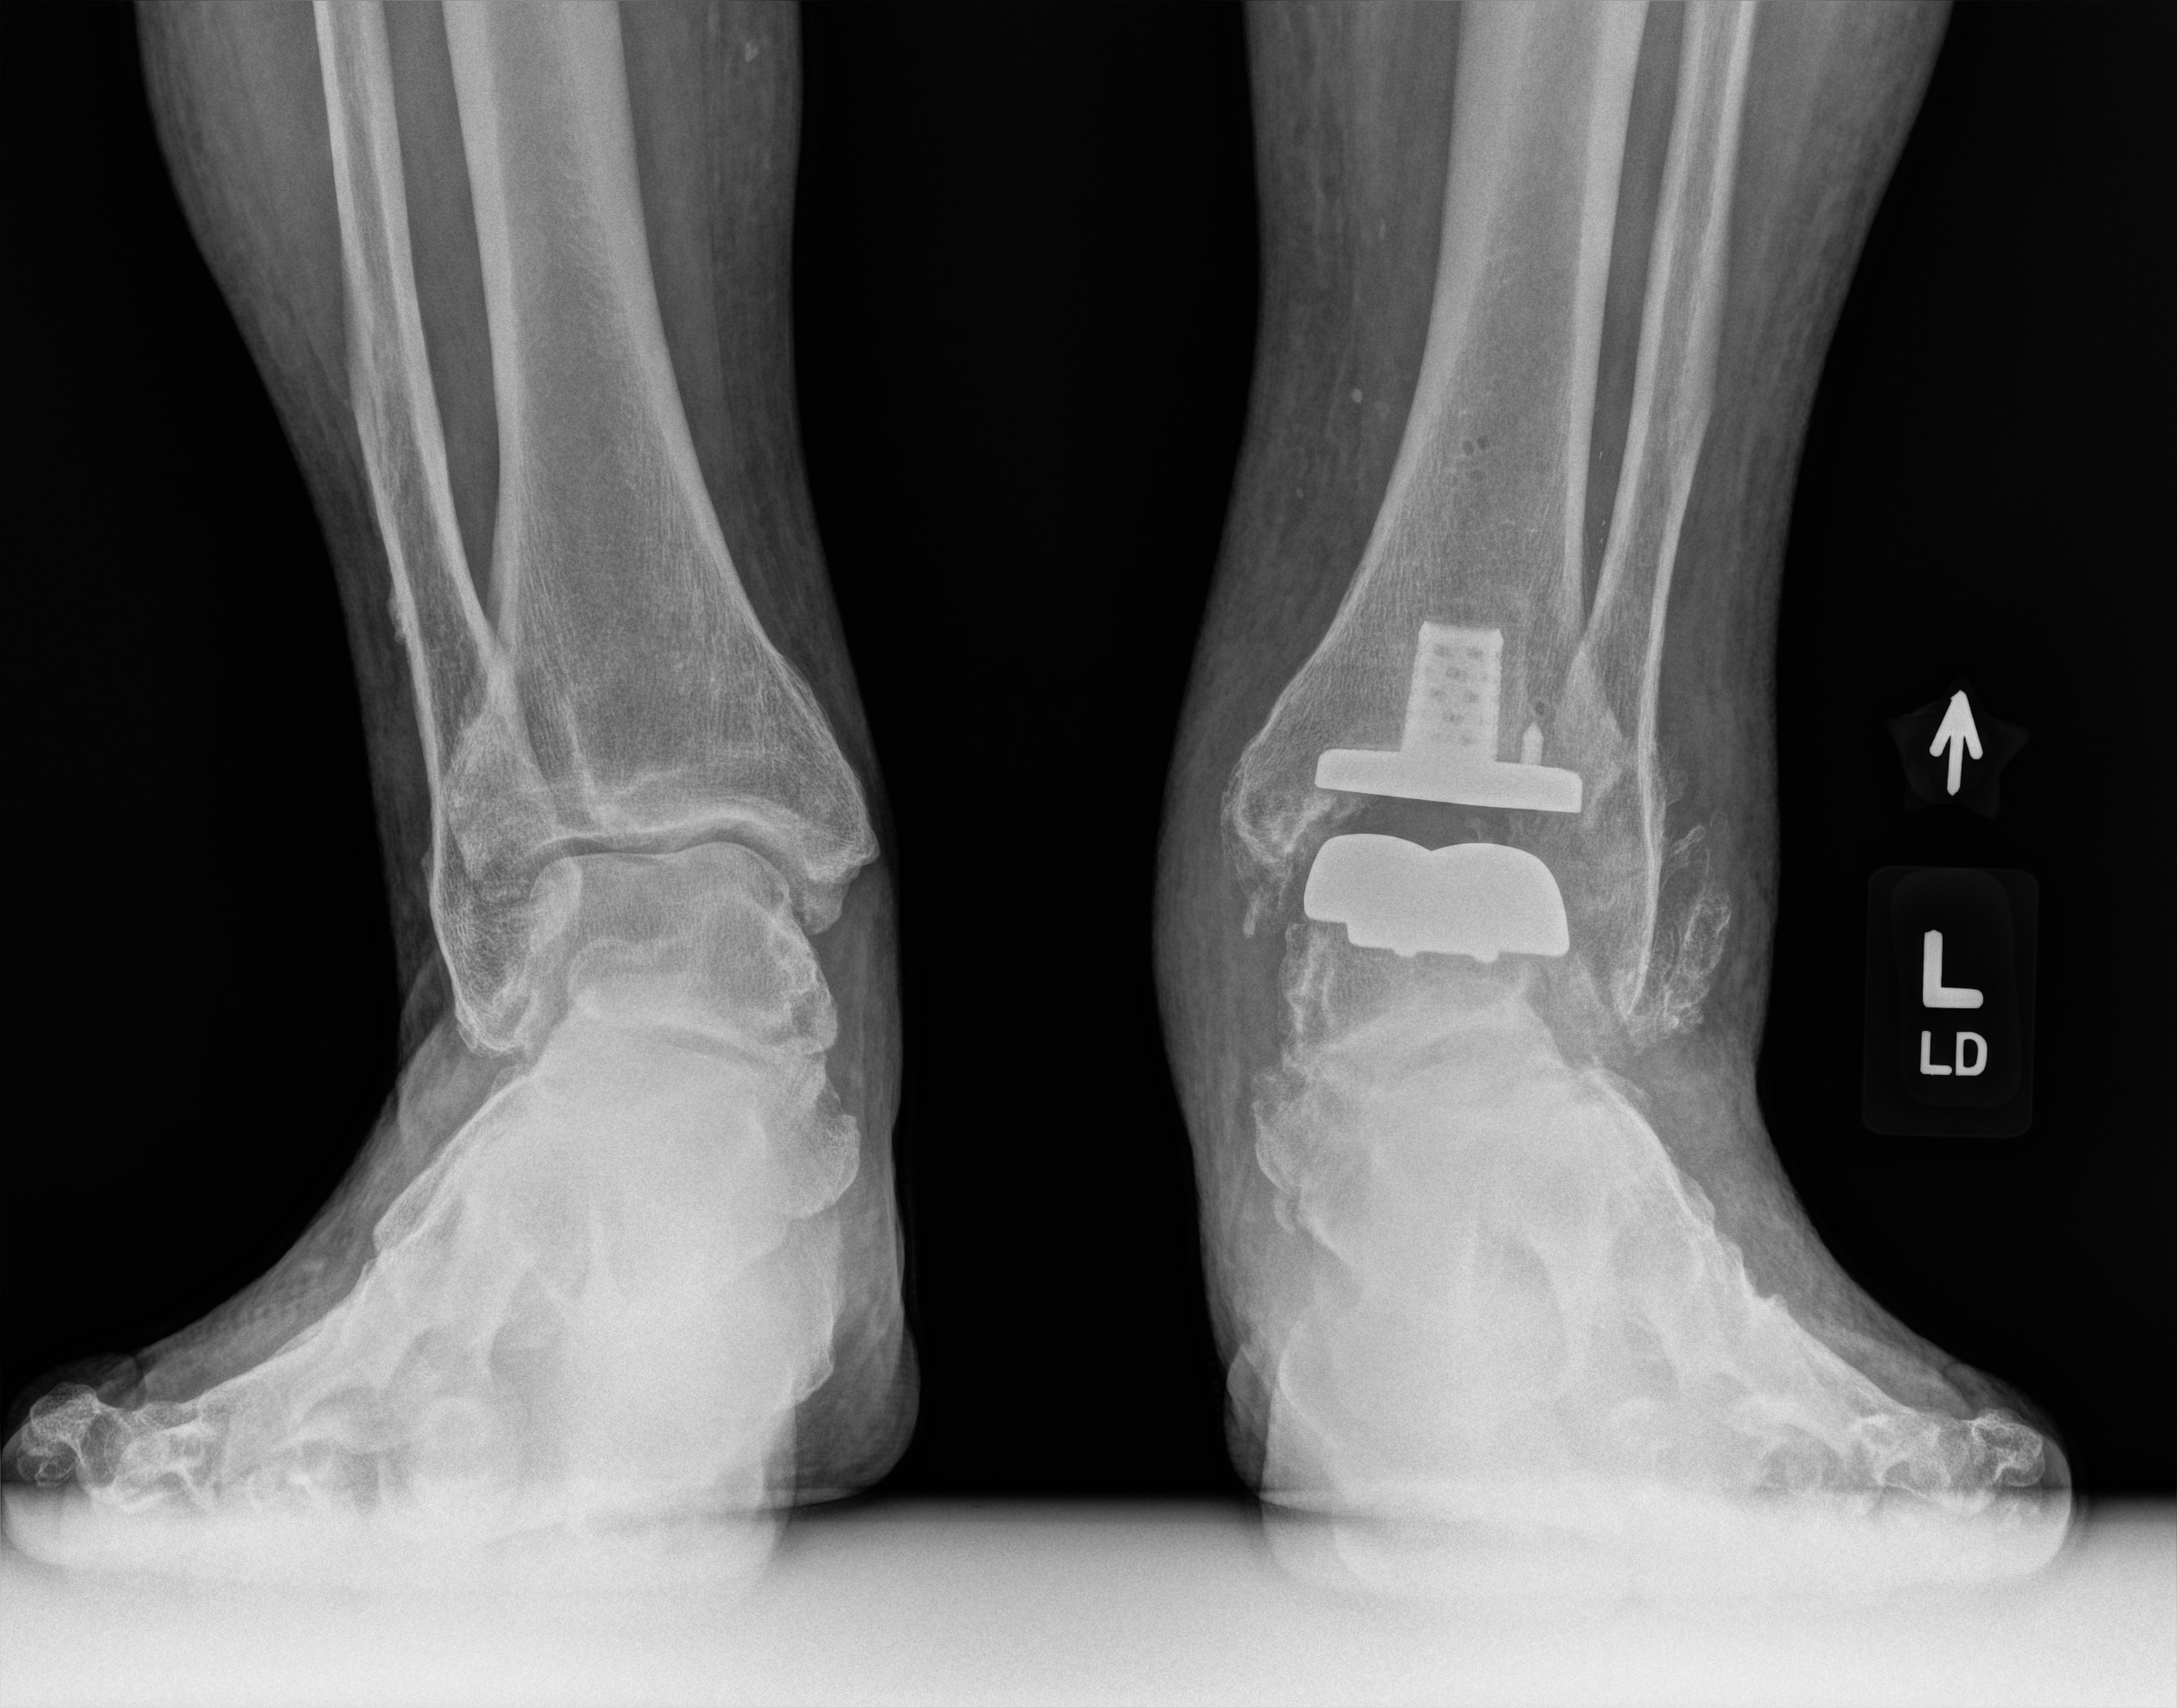

So I had mine done in March... not 100% happy but so much better. Problem is I let mine go for too long (maybe you too) I didn't have some muscles and I need them to walk correctly. Best part is most of the major pain is gone...

This is what I got (video is my doctor): Exactech Vantage Total Ankle System

These were my latest xrays...

• image_8.jpg

image_8.jpg

1.1 MB · Views: 83